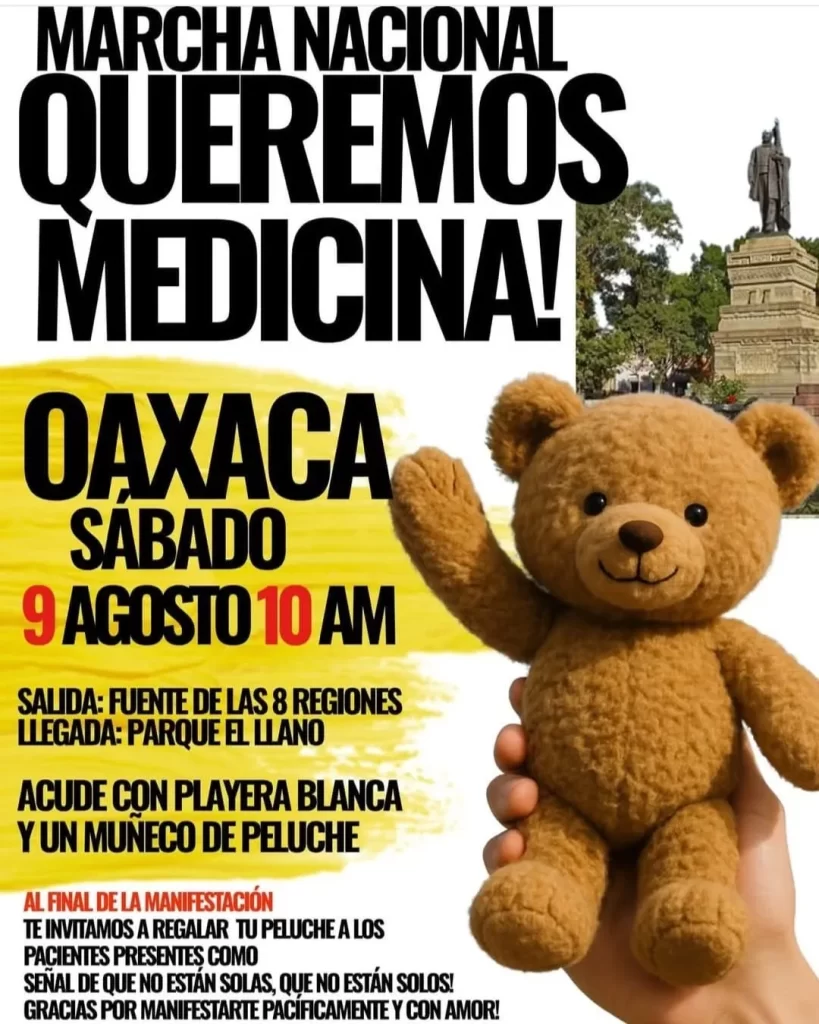

Convocan en Oaxaca a marcha pacífica en defensa del derecho a la salud

Bajo el lema “¡Oaxaca nos necesita!”, ciudadanos y colectivos han lanzado una convocatoria abierta para participar en una marcha pacífica por la salud.